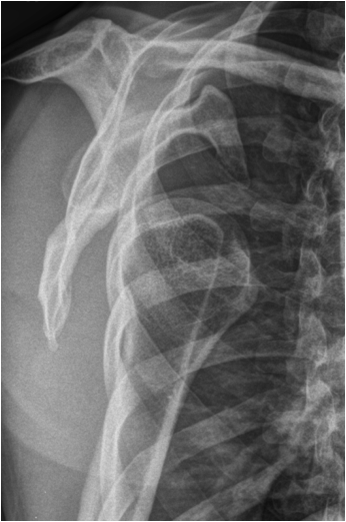

When the range of normal relationships for a particular joint is slightly exceeded, it is called a subluxation. When it is grossly exceeded, and the articulating structures are not in contact any more, it is called a dislocation. Joints most frequently affected by a luxation are shoulder, elbow, ankle, hip, and interphalangeal joints. Luxation will usually cause capsule and ligament disruption with soft tissue swelling and loss of fat planes. Associated avulsion fractures are frequently seen. As in fracture imaging exposure in two perpendicular planes are required to correctly visualize and describe a luxation or dislocated fracture.

Fig. 12. A) Complete dislocation with contraction in the elbow joint. Ulna and radius are both dislocated and dorsally displaced. B.) Anterior and inferior dislocation of the humerus.